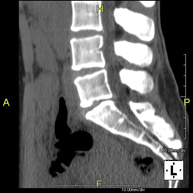

Radiological test that provides high definition anatomical images of the cervical vertebrae using CT (Computed Tomography) equipment. Indicated for: cervical pain without/with irradiation to the arms, trauma.

Prueba radiológica que consiste en obtener imágenes de las vértebras dorsales de alta definición anatómica mediante el empleo de un equipo de TC (Tomografía Computarizada). Indicaciones: dolor dorsal, estudio de desviaciones de la columna, traumatismo. - TC Columna lumbar

Prueba radiológica que consiste en obtener imágenes de las vértebras lumbares de alta definición anatómica mediante el empleo de un equipo de TC (Tomografía Computarizada). Indicaciones: dolor lumbar sin/con irradiación a piernas, dificultad para caminar, traumatismo. - TC Sacro-cóccix